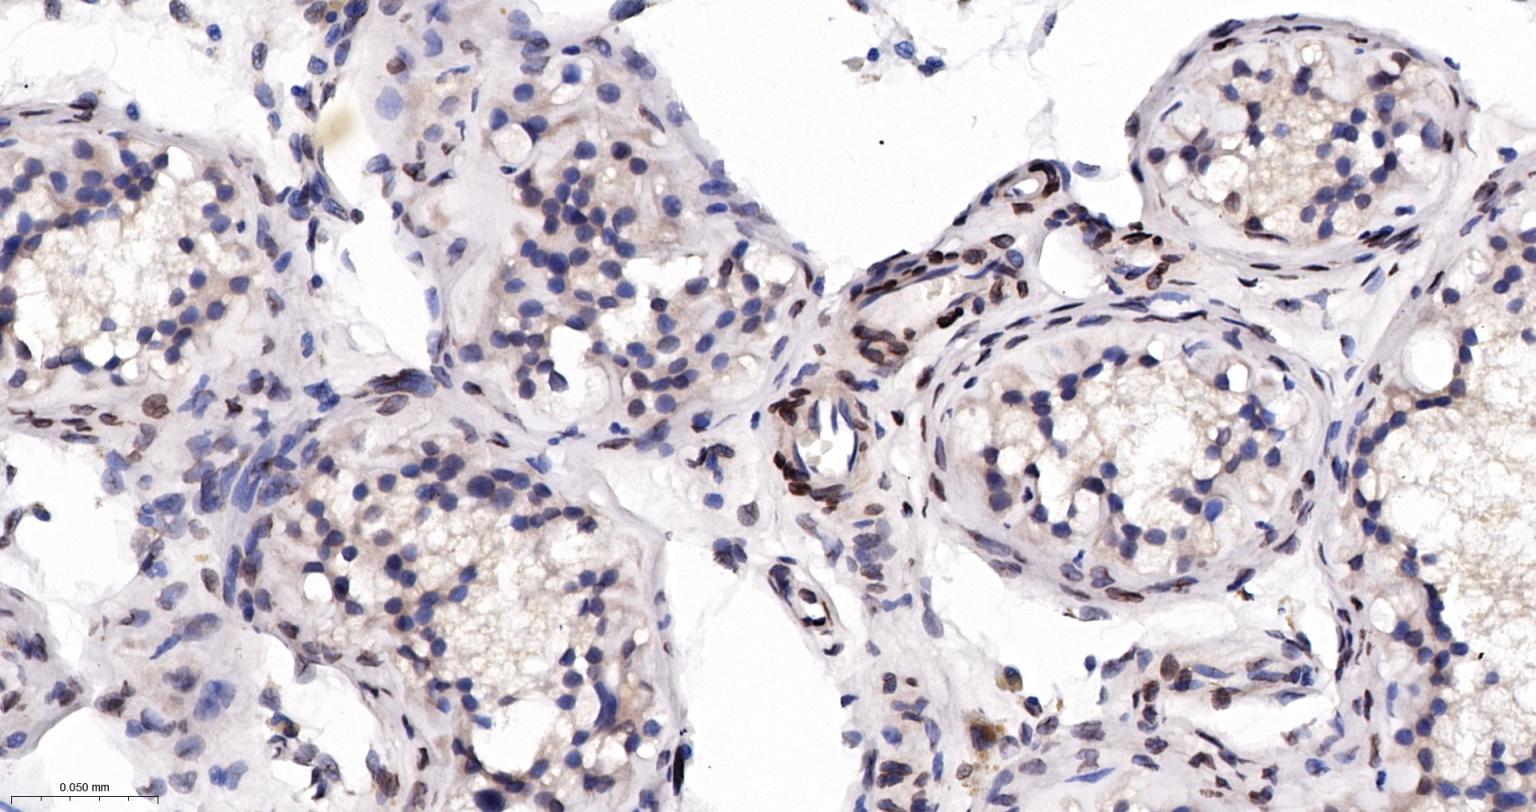

Paraformaldehyde-fixed, paraffin embedded Human Testicles; Antigen retrieval by boiling in sodium citrate buffer (pH6.0) for 15 min; The section was incubated with SUN1 Monoclonal Antibody, Unconjugated (bsm-63252R) at 1:200 overnight at 4°C, followed by conjugation to the bs-0295G-HRP and DAB (C-0010) staining.

Paraformaldehyde-fixed, paraffin embedded Human Ovarian Cancer; Antigen retrieval by boiling in sodium citrate buffer (pH6.0) for 15 min; The section was incubated with SUN1 Monoclonal Antibody, Unconjugated (bsm-63252R) at 1:200 overnight at 4°C, followed by conjugation to the bs-0295G-HRP and DAB (C-0010) staining.

Paraformaldehyde-fixed, paraffin embedded Human Colon Cancer; Antigen retrieval by boiling in sodium citrate buffer (pH6.0) for 15 min; The section was incubated with SUN1 Monoclonal Antibody, Unconjugated (bsm-63252R) at 1:200 overnight at 4°C, followed by conjugation to the bs-0295G-HRP and DAB (C-0010) staining.